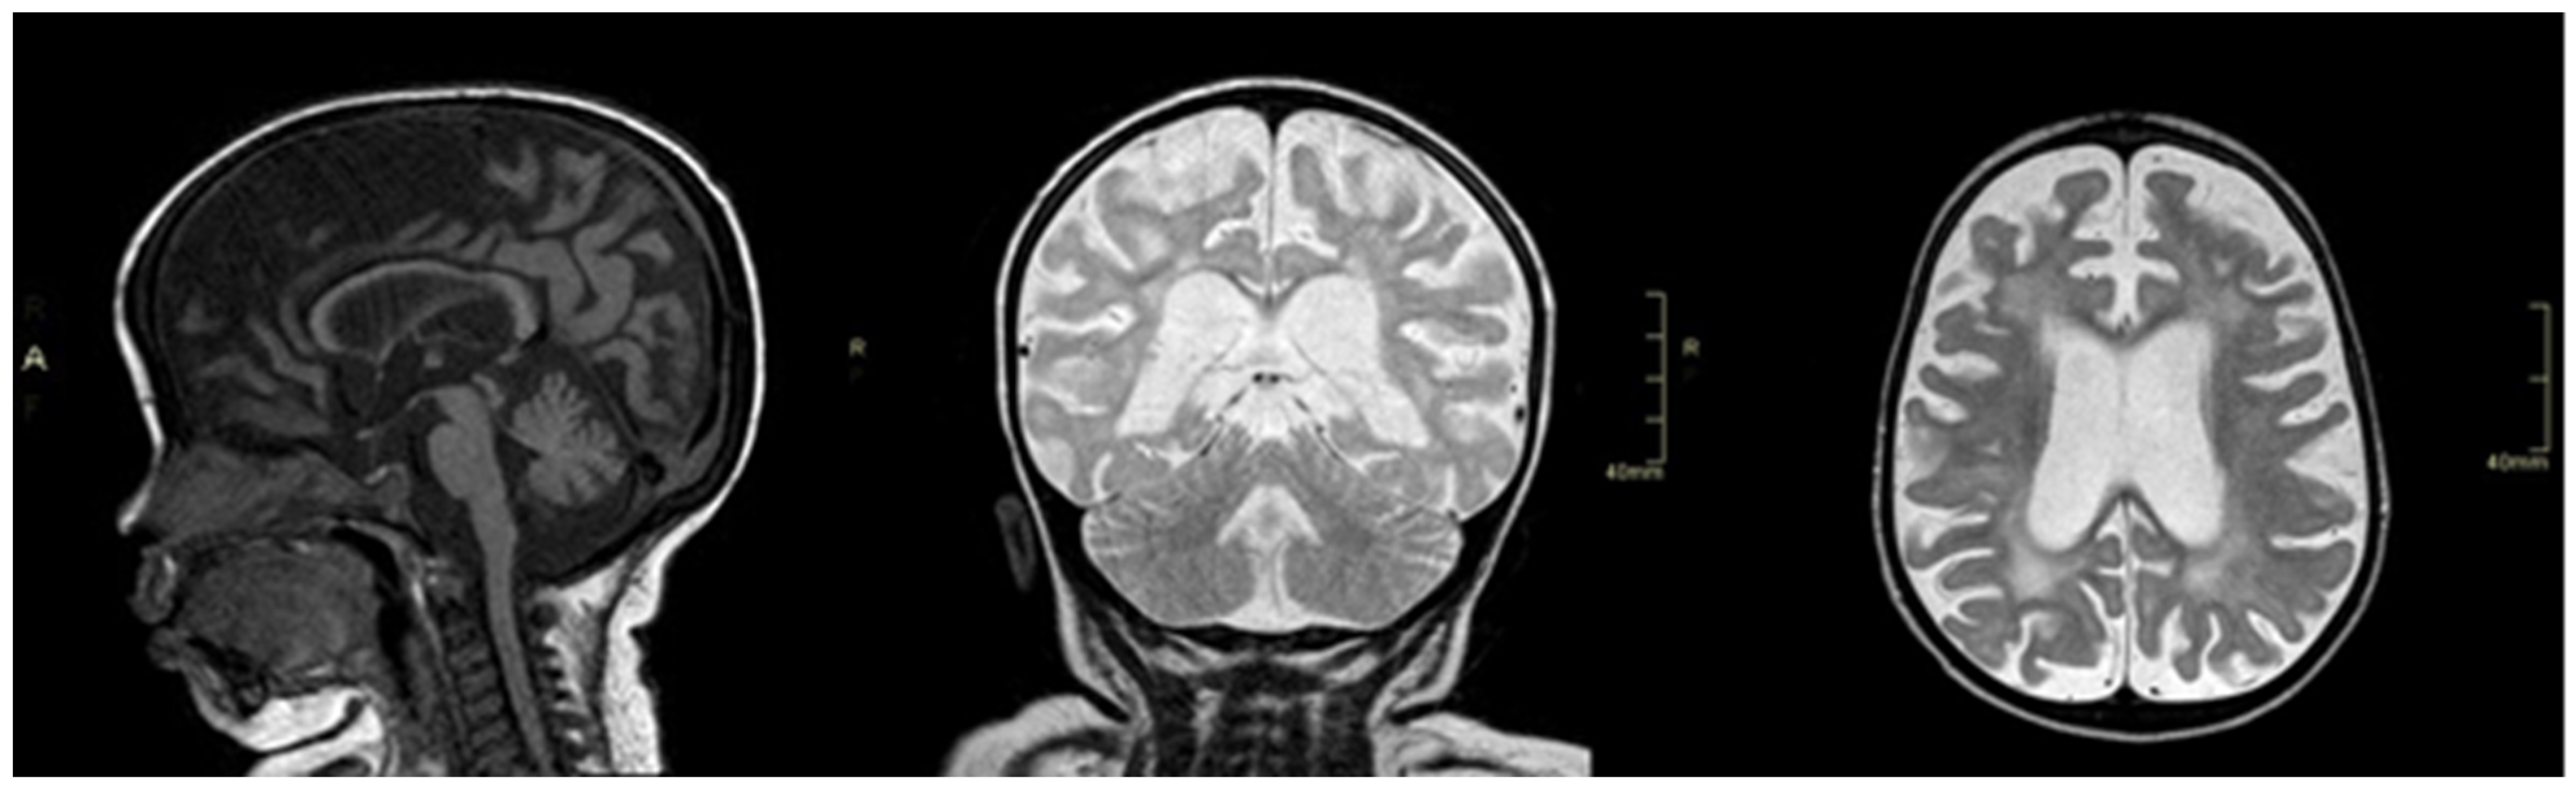

2. Case Report